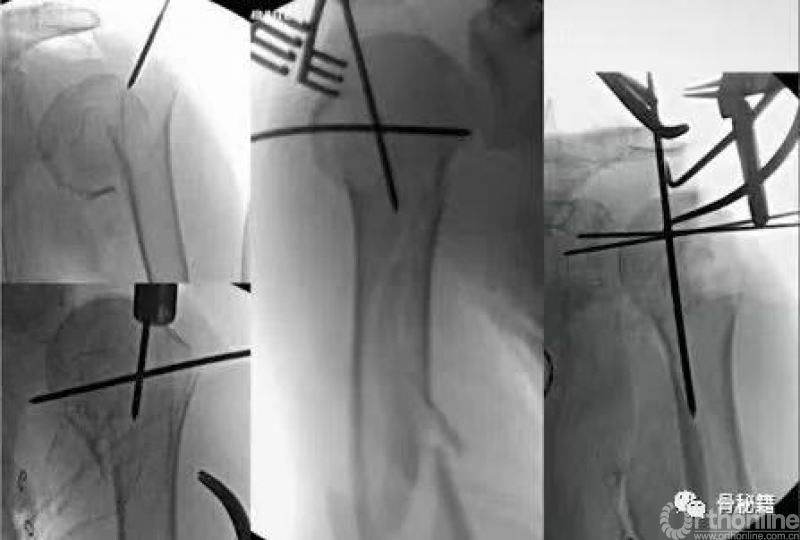

复位的关键就是将低头的肱骨头敲拨起来,外翻到合适的位置

可以应用摇杆技术等进行肱骨近端的复位,同时需要注意避让进针点的位置

也可以应用鞋拔子来进行翘拨复位,但是需要注意的问题是

外侧骨块必须是完整的,内侧一定要足够深入到头下的位置在骨量较好的地方进行翘拨